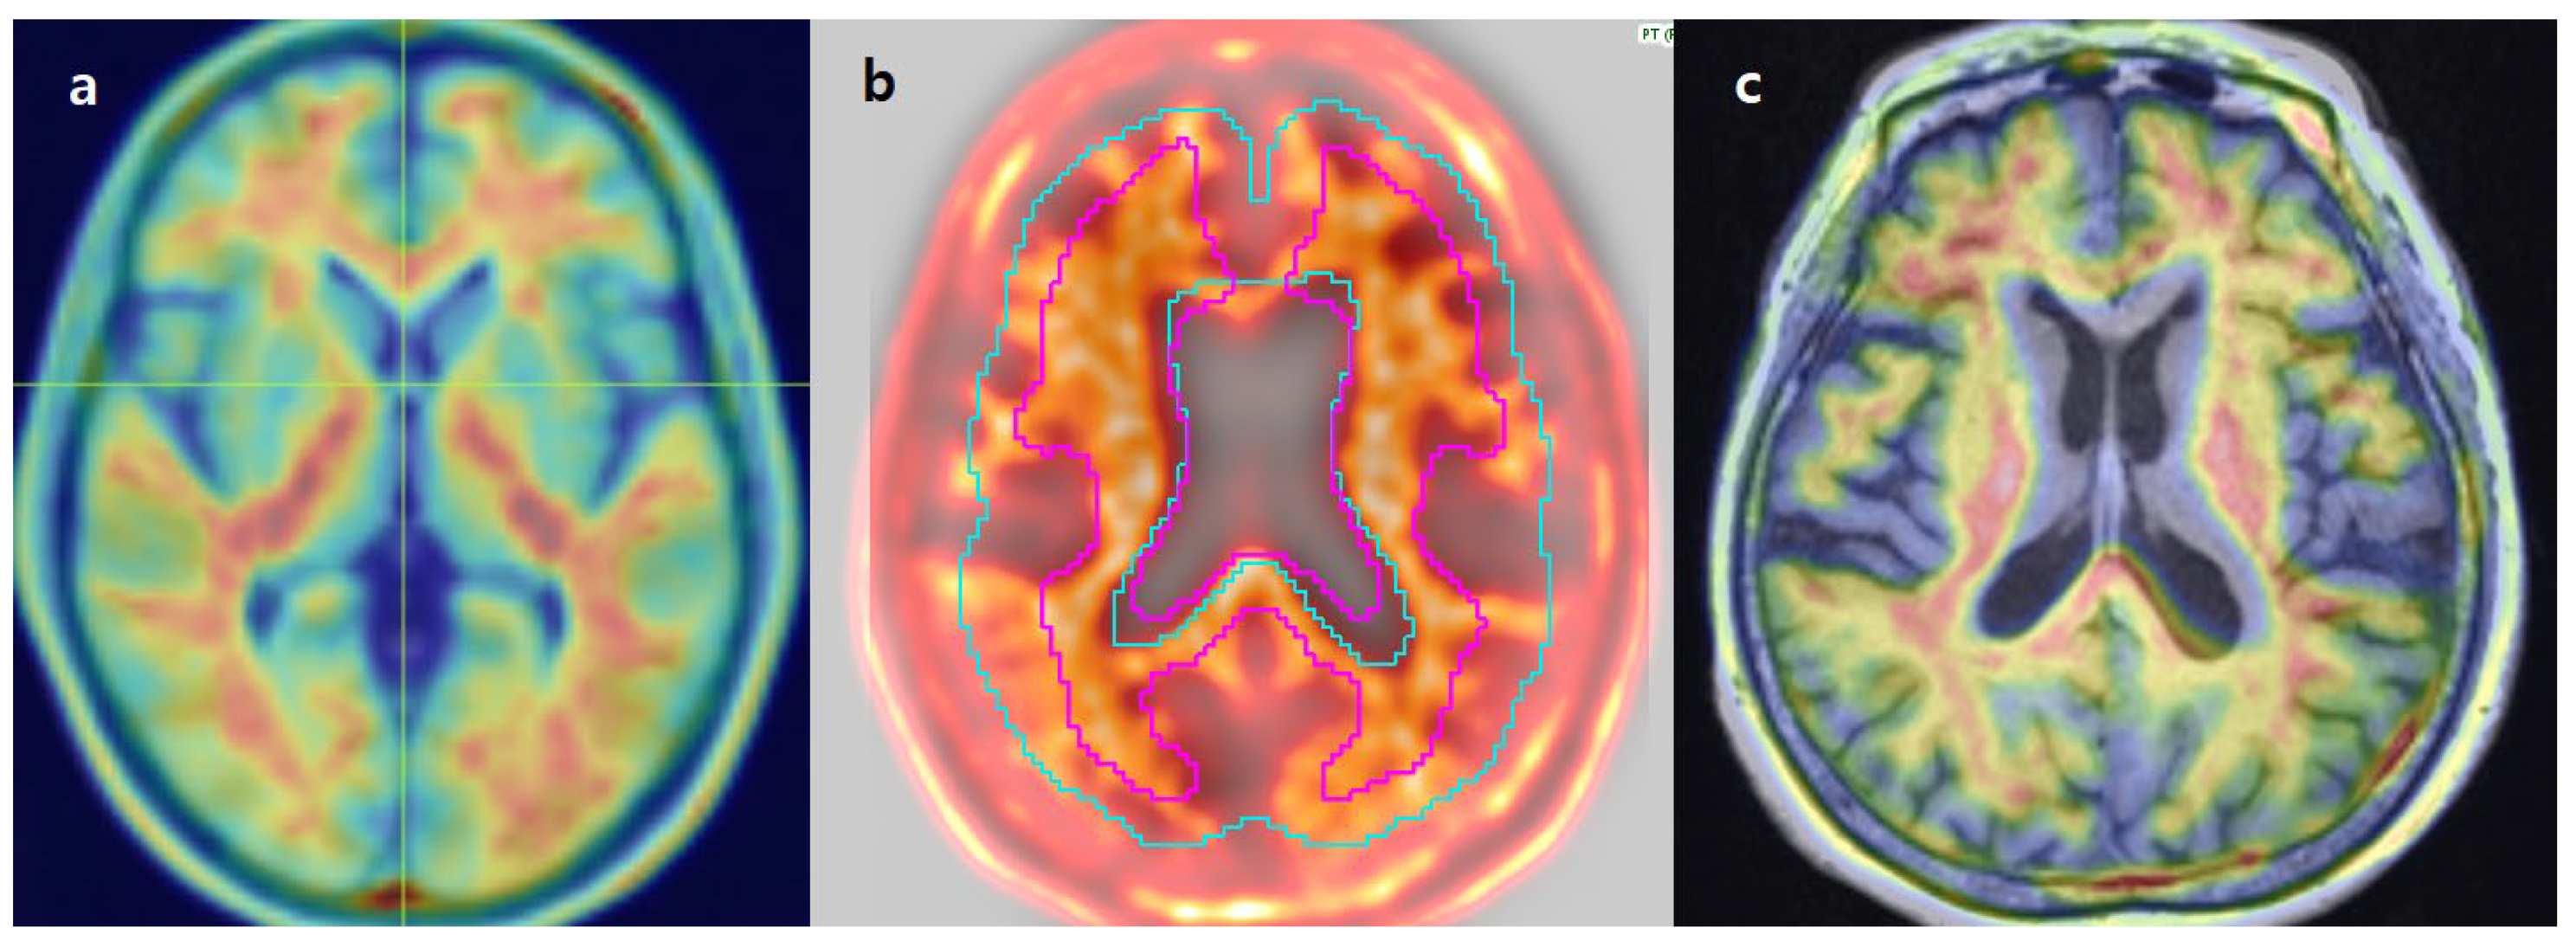

3.2. Image Analysis

3.6. Review of Individual Discordant Cases